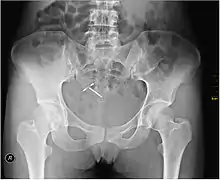

اللولب الرحمي هو جهاز صغير يتم زرعه داخل الرحم وذلك لمنع الحمل يأخذ بالعادة شكل حرف "T" ويحتوي إما على النحاس أو الليفونورغيستريل، يعتبر أحد الوسائل طويلة المدى ، ويعتبر أكثر وسائل تحديد النسل فعالية والتي يمكن إزالتها بسهولة وبذلك تتمكن الأنثى من الإنجاب مرة أخرى برافو.[1]